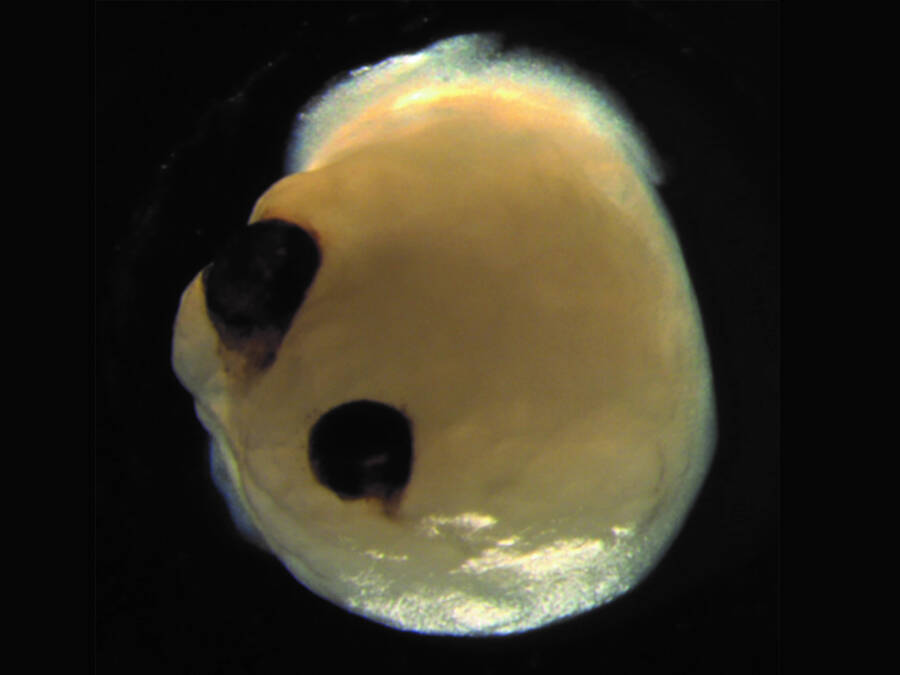

Gabriel et al., Cell Stem Cell, 2021Brain organoids a mere 60 days after stem cell introduction.

The prow cellular phone in the Petri dish culture visibly evolved into brainpower cells within 30 day and matured into tiny brains with rudimentary oculus structures by the 50th day . While that accomplishment mirror the development timeframe of centre in the human fertilized egg , the more amazing result was that these optic could in reality see .